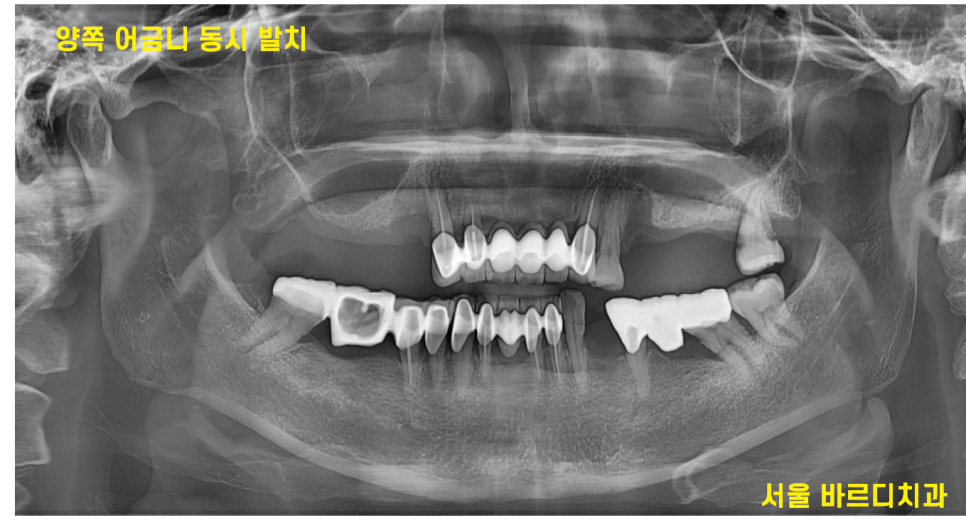

231021

우선 문제가 되는 양쪽 브릿지 발치를 진행

잇몸뼈가 없다보니 발치와 동시에 뼈이식을 진행하였습니다.

발치 당일에 임플란트를 심을 수 없어

뼈이식부터 해놓고

치유를 기다린거죠~